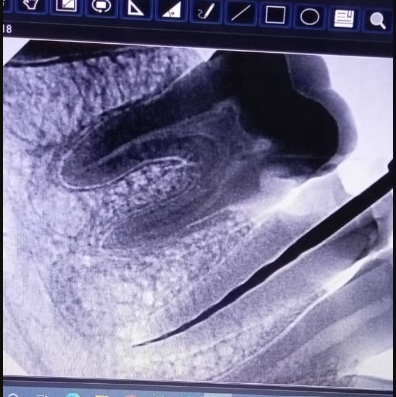

Missing tooth replaced with a permanent dental implant for natural function and aesthetics.